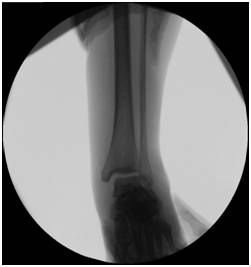

Radiological assessment shows

L3 unstable spine fracture, Right intara-articular calcaneal fracture of joint depression type, Saunder’s III AC3,4(Figure 1 & 2).

Figure 1 CT Calcaneus showing multi fragmentery intra articular fracture.

Figure 2 CT Calcaneus showing joint depression and intra articular extension.